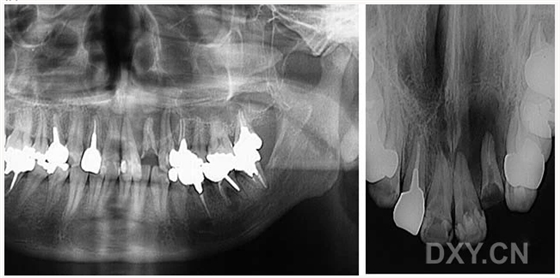

球狀上頜囊腫

含牙囊腫

球狀上頜囊腫    含牙囊腫